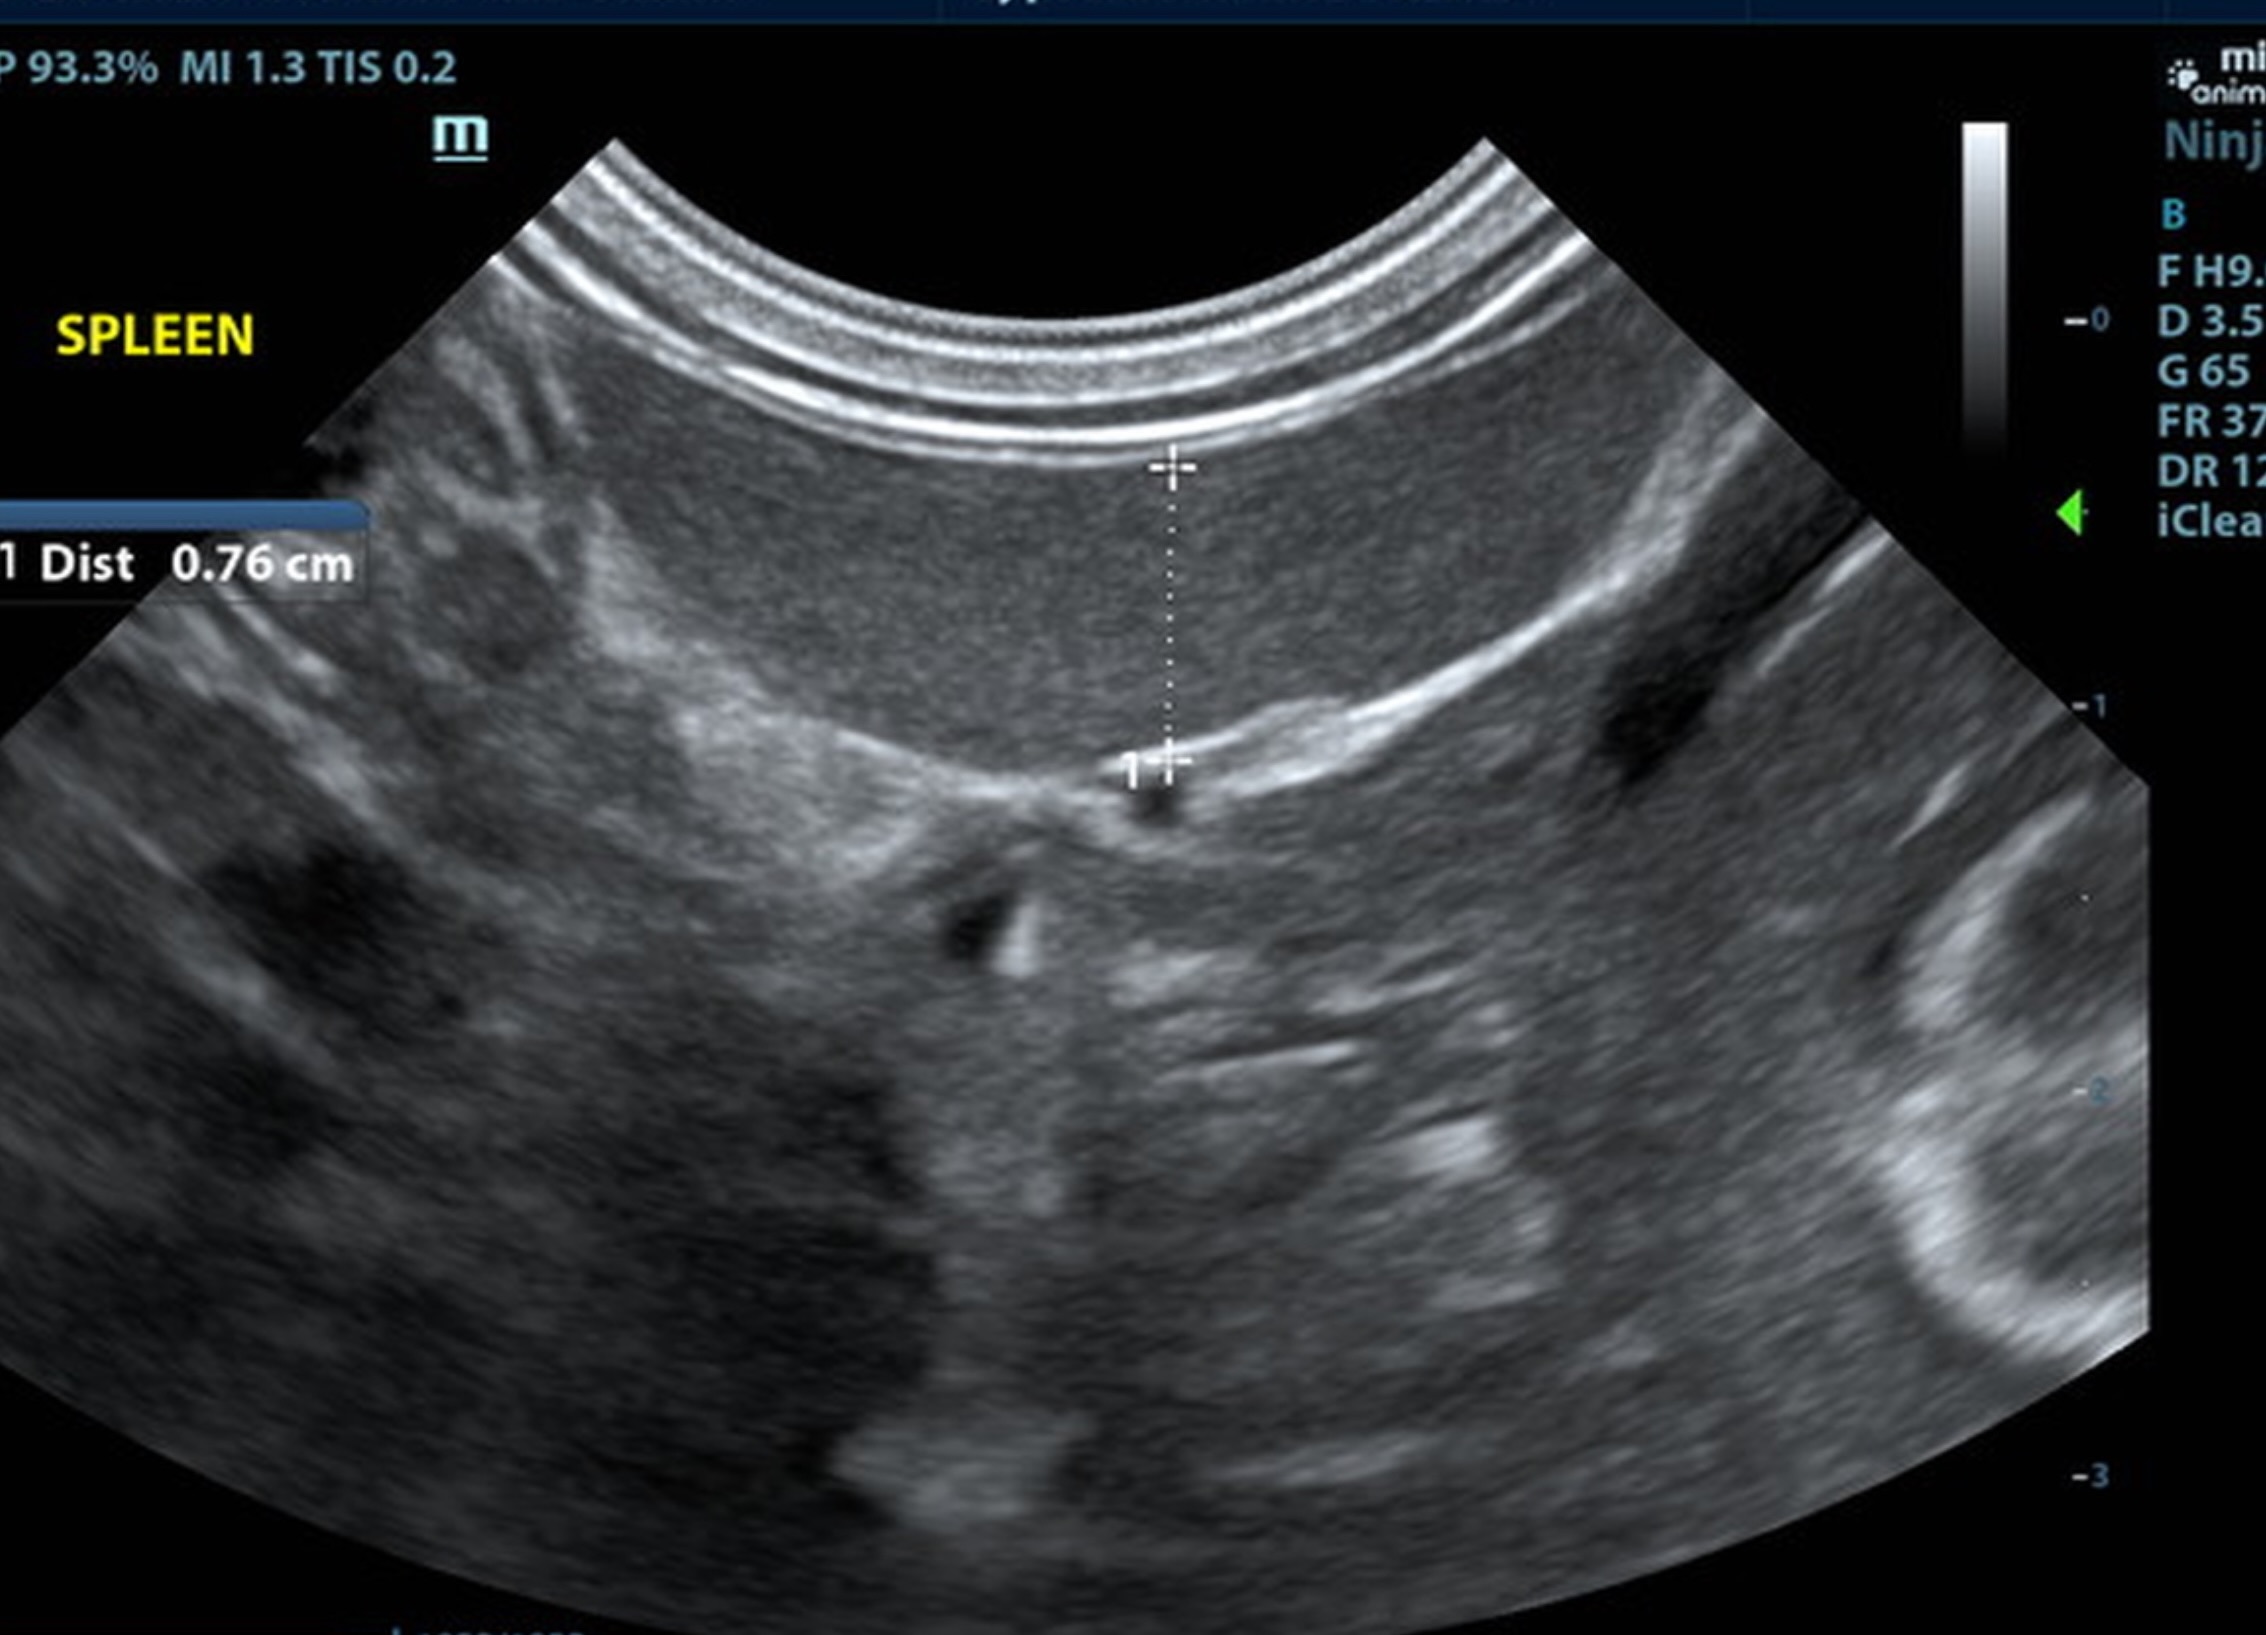

The liver was subnormal in size, yet the portal vein and vena cava ratio was 1:1. The portal veins were subnormal in size and measured 0.34 cm. The vena cava was enlarged and measured 0.34 cm. The vena cava was enlarged and measured 0.72 cm, aorta measured 0.4 cm. The branching of the portal vein appeared to be normal and of adequate volume. The portal vein and vena cava measured 0.5 cm each in the extrahepatic space. The splenic vein entry into the portal vein and gastroduodenal vein entry into the portal vein appear to be normal. There was one turbulent vessel in the region of the central branch of the portal vein, which may represent an intrahepatic shunt, but this could not be confirmed. The width of the shunt is approximately 0.76 cm. This is in position of central divisional shunt; however, right divisional origin cannot be completely ruled out. The gallbladder presented acceptably thin walls with primarily anechoic content. The cystic and common bile ducts were normal.